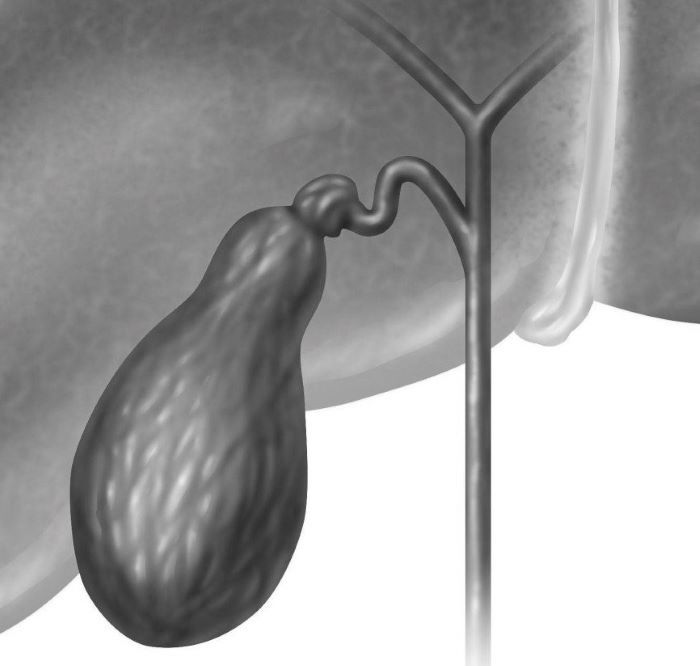

Анатомия и особенности Гартманова кармана желчного пузыря